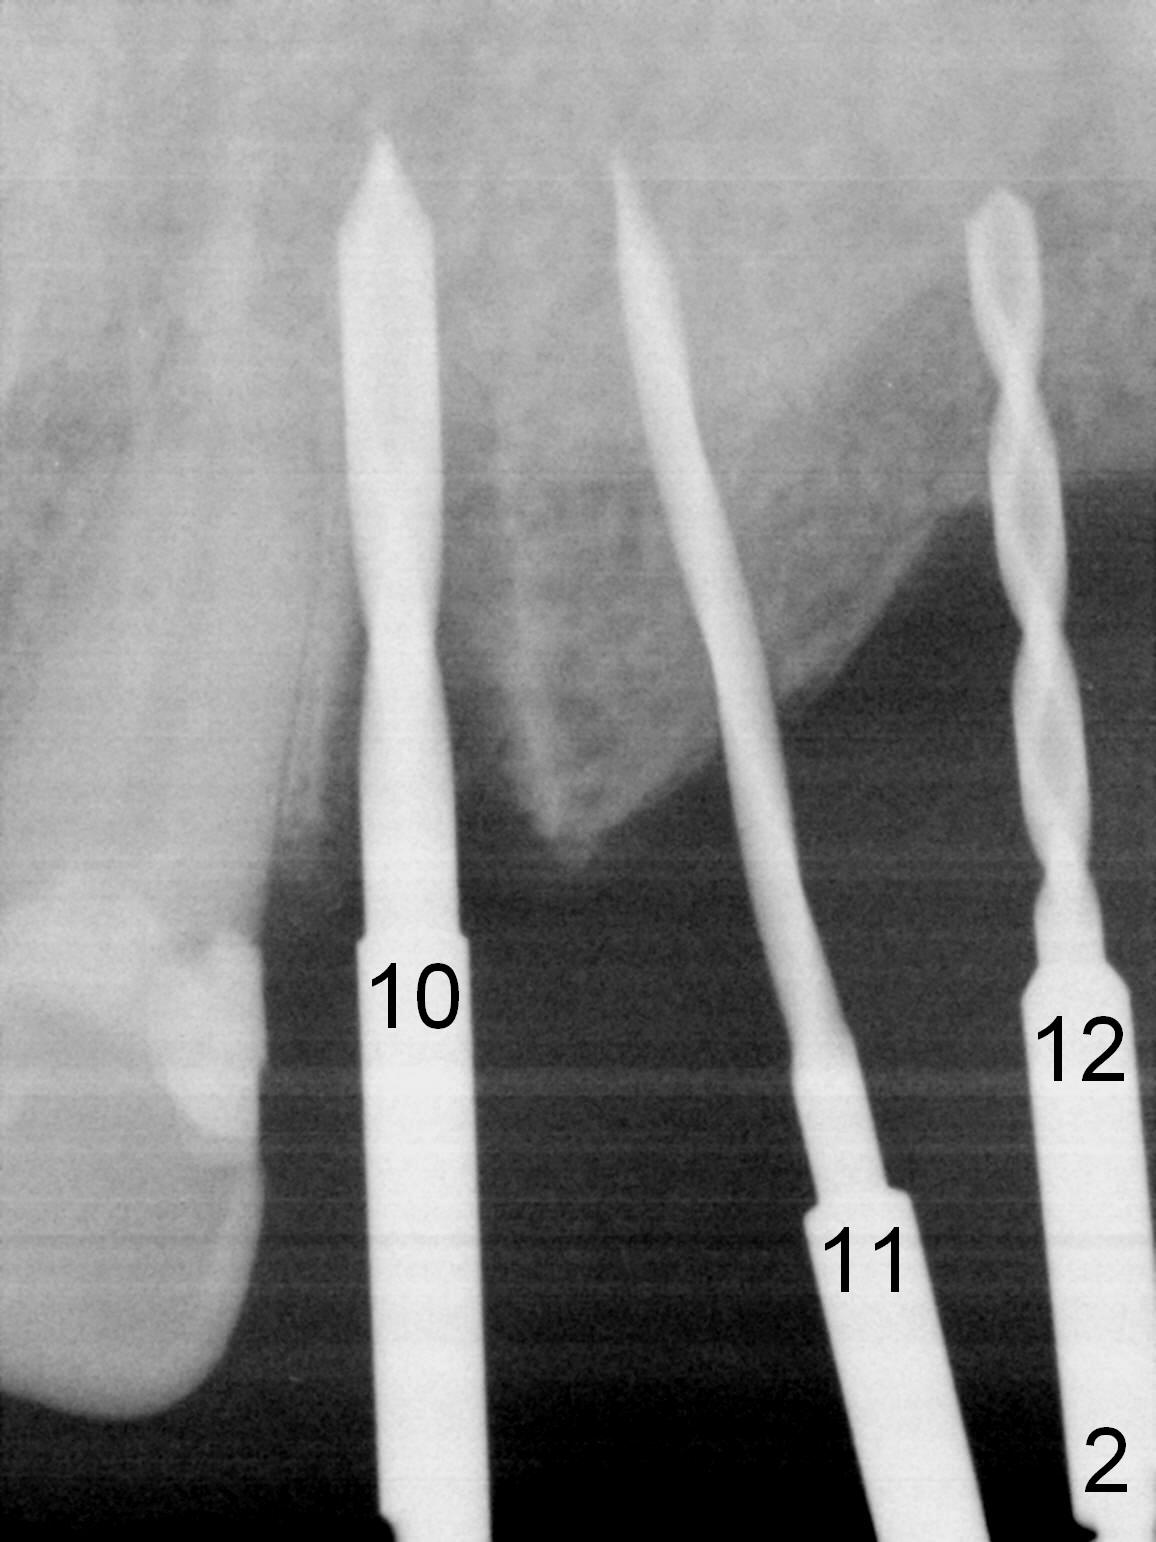

When the patient returns for implant placement (2nd visit after initial exam), he reveals that he is a dental phobic.  He requests placement of 4 implants in the upper left quadrant, instead of 2.  Narrow ridge is unexpected in the canine and premolar area (Fig.1).  Limited bone height at #13 (Fig.3 arrowheads: sinus floor) is found when initial drills are in place (Fig.2,3).  A 2-piece implant (4.5x17 mm tissue-level) is placed at #10 after extraction, while 1-piece implants are placed at 11 (3x17 mm (tissue-level, 15 °) and 12 and 13 (bone-level, 2.5x14, 12 mm, respectively; Fig.4,5).  In fact the 1 piece implant at #13 is not completely placed (Fig.5).  It is removed, the apical 3 threads are cut off (Fig.6 <, since a shorter implant was unavailable in the office) and the remaining implant is re-inserted.  The insertion torques of the 4 implants are ~ 60, ~ 35, < 35 and 15 Ncm, respectively.  After adjustment (Fig.7), immediate provisionals are fabricated at #10 and 11 (Fig.8, later splinted with composite), while perio dressing is applied around the implants at #12 and 13 and the provisionals at #10 and 11.  There is no nasal hemorrhage postop.  Although the perio dressing is loose 1 week postop (Fig.9), it is not removed.  When the upper lip fissure (Fig.9 <) heals, provisionals at #12 and 13 are planned to be splinted to the other two ones.  Two weeks postop, the upper lip fissure heals, the perio dressing dislodges and the implants at #12 and 13 are stable (Fig.10).  After abutment height adjustment, a splinted provisional is fabricated over these 2.5 mm 1-piece implants (Fig.11).